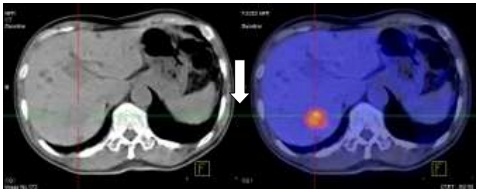

Hình 1.4. Di căn gan kích thước: 3x4cm, SUV=6,9.

Hình 2.6. Trước điều trị: U gan HPT VII KT: 3x4cm, SUV=7,4.

Hình 2.7. U gan phải sau hóa trị kích thước: 2x3cm, SUV=4,1.

Như vậy sau 6 chu kỳ hóa trị kết hợp Bevacizumab: Các tổn thương u nguyên phát, di căn hạch ổ bụng, nốt di căn phổi đã không còn, chất chỉ điểm khối u CA 19-9 giảm. Tuy nhiên tổn thương di căn gan vẫn tồn tại và kích thước tổn thương gan đã thuyên giảm còn 2x3cm.

Tóm lại: Bệnh đáp ứng một phần.